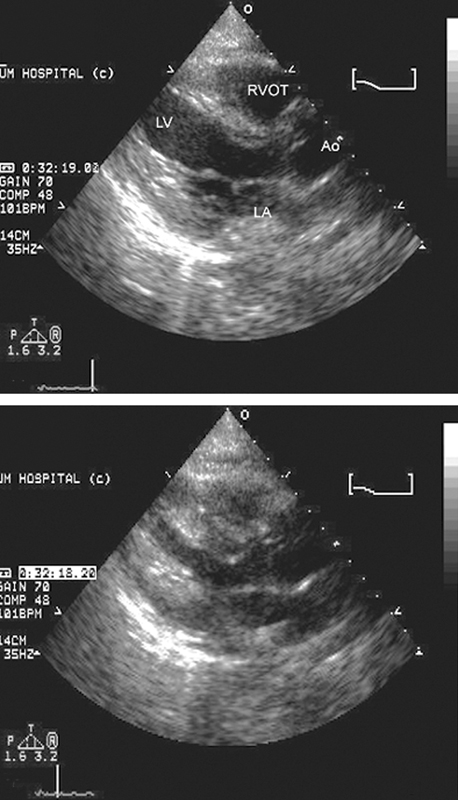

فحوصات تشخيصية لبعض امراض القلب والشرايين التاجية